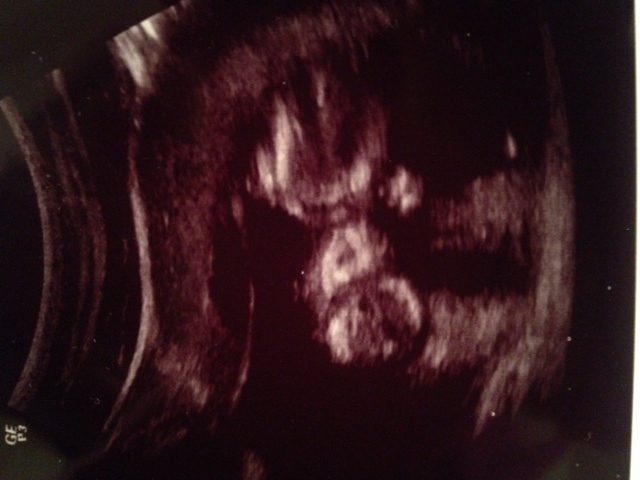

Skull theory from the front?

I have been MIA lately. Between this all day sickness and DD being in Kindergarten and me volunteering almost everyday then coming home and having to play housewife I forgot what the internet was. I had my 12 week appointment last week. They couldn't find the heartbeat so I got another ultrasound and the baby was perfectly fine. He printed me off a picture of the babys face front on. I didn't know if there was a skull theory for the front of the face ... just in case I am going to upload it. If not I have my 13 week NT scan on Wednesday and am hoping the baby cooperates and gives us a good potty shot!Attachment 15191